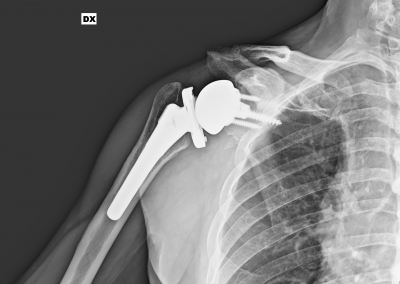

L’artropatia da rottura cronica e irreparabile della cuffia dei rotatori ha la sua espressione radiografica nella artrosi eccentrica dell’articolazione gleno-omerale (“acetabolarizzazione”):

a causa della perdita del centraggio della testa stessa legato alla insufficienza funzionale della cuffia

Perché funziona una protesi inversa:

Medializza e abbassa il centro di rotazione della articolazione gleno-omerale per cui incrementa il braccio di leva del deltoide (che diventa il vero motore per la elevazione e abduzione) dato che la glenosfera è direttamente appoggiata sulla glenoide, non esiste un braccio di leva che determini delle forze di taglio, anzi durante la abduzione e la elevazione i muscoli danno un effetto centratore e stabilizzante sulla protesi